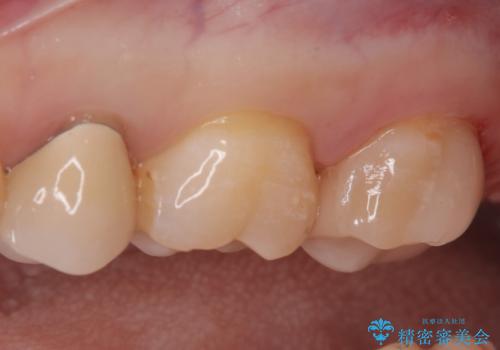

【セラミックインレー】適合の良い修復

- 定期検診にて虫歯が見つかった患者様です。

金属のインレーの下と、歯と歯の間も虫歯だったため、つなげた形でセラミックインレーにて修復を行なっています。

e-max プレスインレーを用いることで、適合の良い治療ができます。